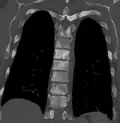

Osteosclerosis can be detected with a simple radiography. There are white portions of the bone which appear due to the increased number of bone trabeculae.